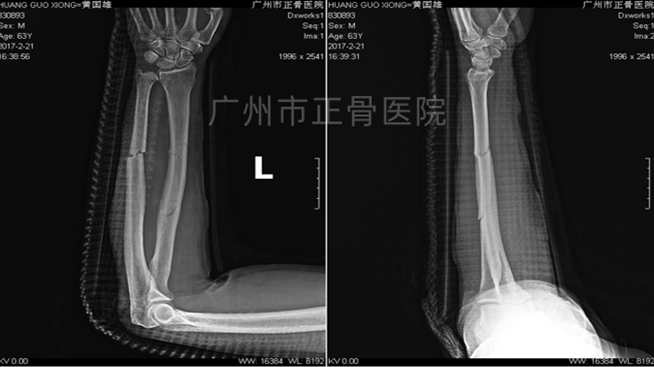

▲1周后,骨折端稳定

▲4周后,骨折端稳定,少量骨痂生长